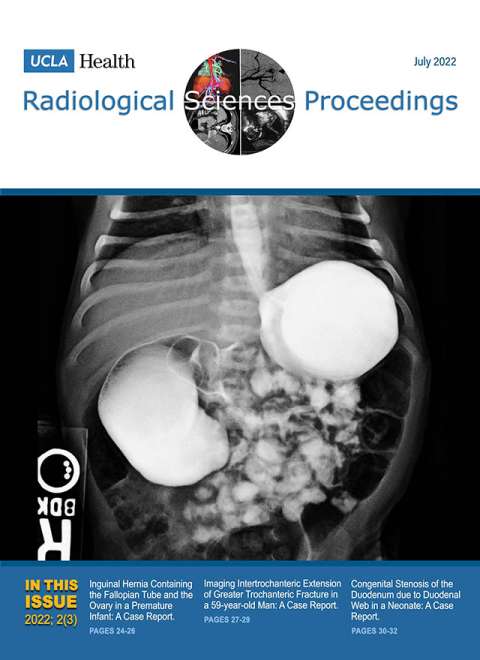

July 2022

Volume 2, Issue 3

- Inguinal Hernia Containing the Fallopian Tube and the Ovary in a Premature Infant: A Case Report

- Imaging Intertrochanteric Extension of Greater Trochanteric Fracture in a 59-year-old Man: A Case Report

- Congenital Stenosis of the Duodenum due to Duodenal Web in a Neonate: A Case Report